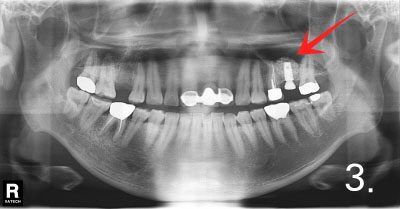

There is not enough bone to place implant on upper and left side.

Performed sinus graft more than 90% of bone required to place implant

Placing implant in bone graft site

Implant crown was fabricated